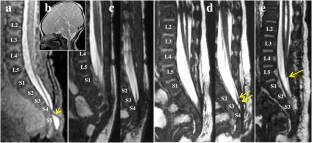

We report an additional patient with RMC, in whom a congenital dermal sinus (CDS) was found in the caudal portion of the RMC. At the age of 3 days, the patient underwent surgery consisting of meningocele excision and cord untethering, and CDS was noted histologically in the proximal cut end of the RMC. During a second surgery at the age of 5 months, after determining the exact border of the nonfunctional RMC and the true conus by neurophysiological mapping, we removed the entire length of the remnant RMC, including newly developed epidermoid cysts in the CDS.